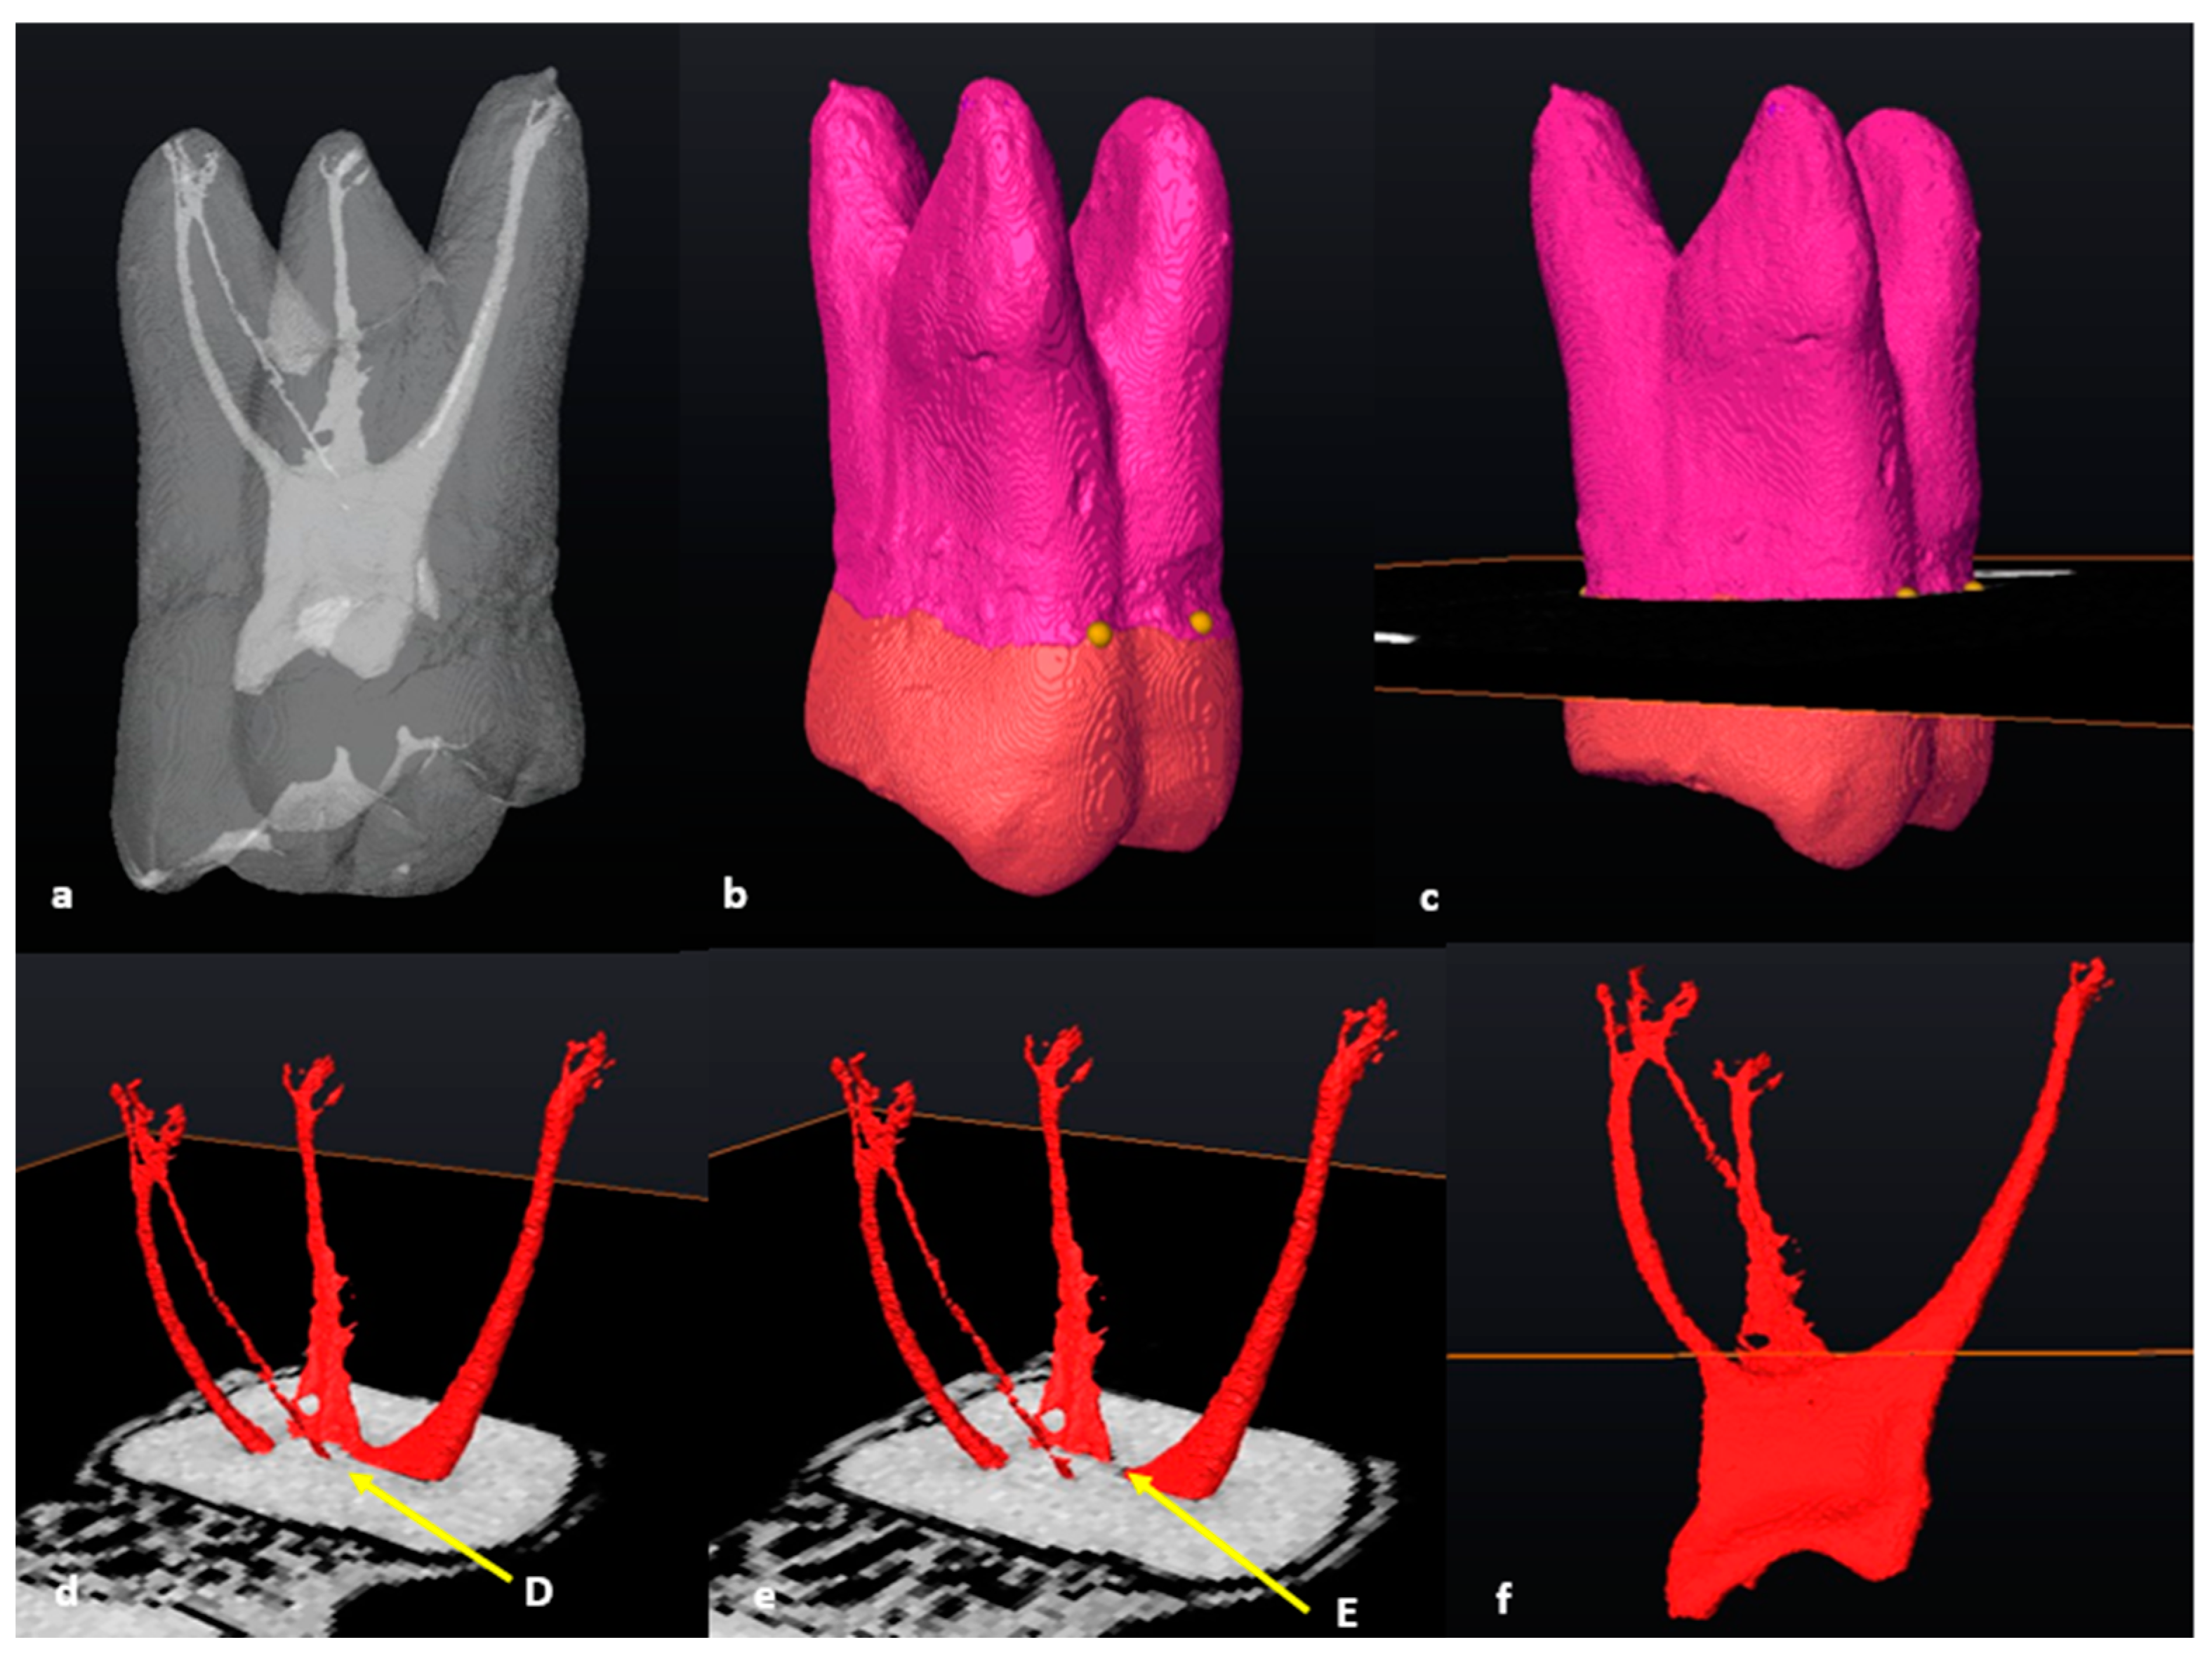

3.5. Fused Roots